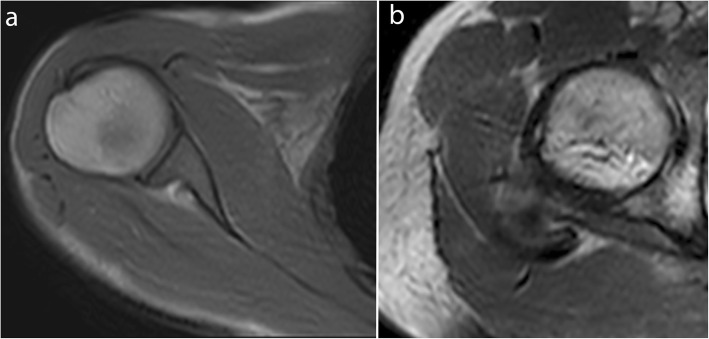

Fig. 1.

Real-time dynamic MR images obtained with balanced SSFP sequence at 3.0 T. Shoulder in the axial plane in external rotation (a) and hip in the axial plane in external rotation (b) (TR, 4.2; TE, 2.1; flip angle, 40°; pixel size, 1.37 × 1.83 mm)